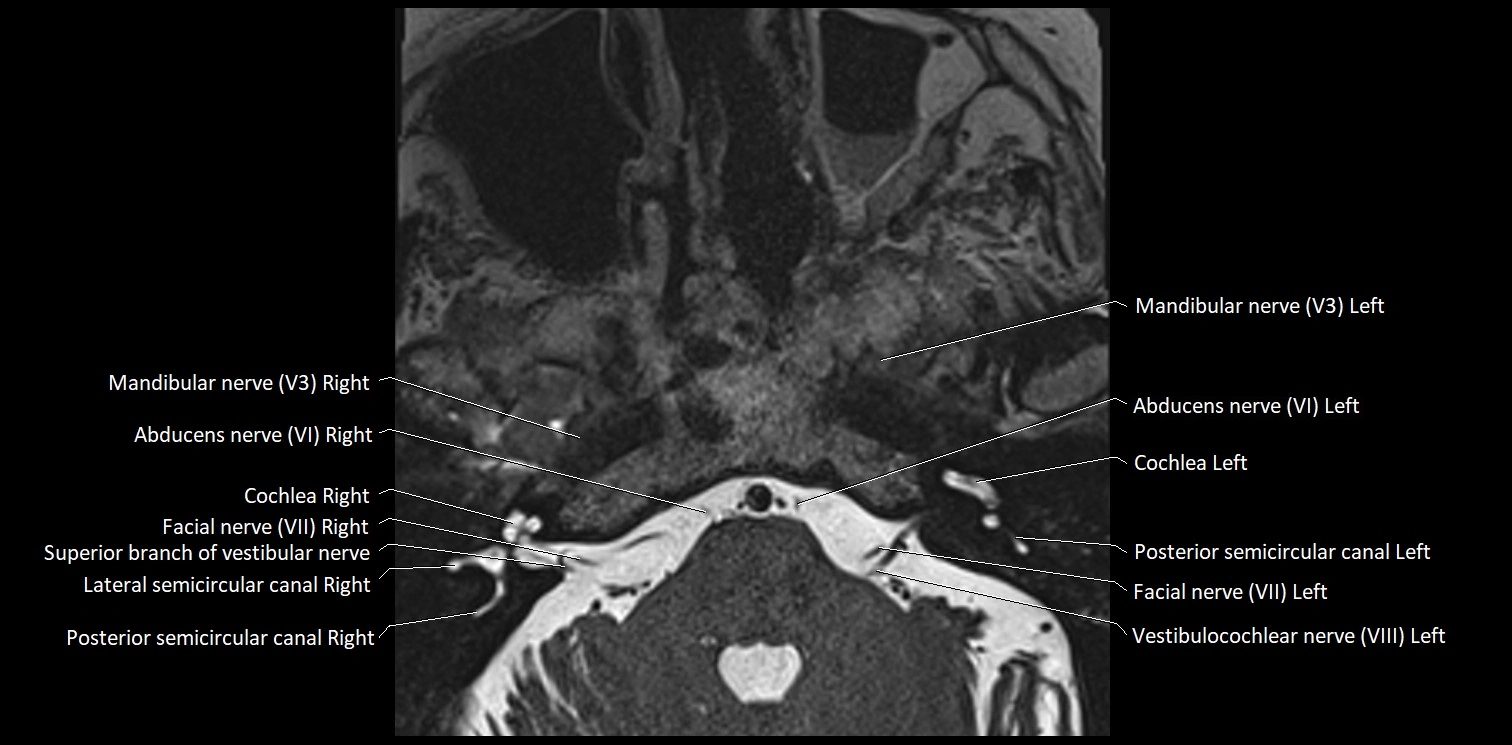

MRI images

image